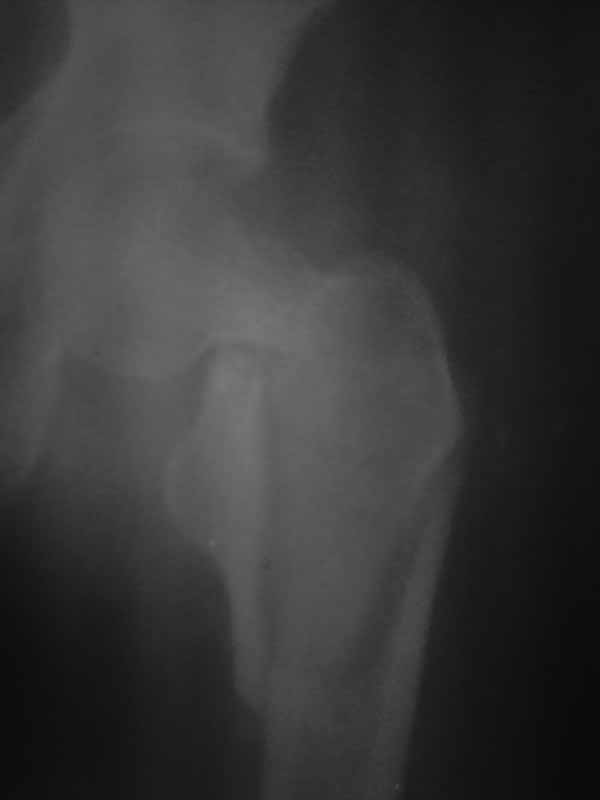

Снимок, конечно, паршивый - лучше было повременить с размещением вопроса до возможности сопроводить его нормального качества иллюстрациями.

Перелом идет на диафиз, так что если придется использовать пластину, то надо длинную, да с угловой стабильностью - клинковую, может.

Тут, видимо, лучше использовать реконструкционный гвоздь - не знаю, какова на месте степень недоступности такого типа имплантатов. Где вы находитесь? Может, попытаться прислать подходящую железку?

Хотелось услышать дискуссию, по-этому выложил некачественный снимок с вопросом. Стараюсь выложить немного лучше. Гамму она приобрести не сможет. Смущает то что шейка больно хлипкая и винтом развалим ее до конца. На снимке кажется что и фрагмент шейки также сломан вдоль.

Доброго времени суток уважаемые коллеги!! Если бы перелом был чрезвертельным то все примерно было бы понятно. Гамму пациентка не купит, больница тоже ее не купит. Я попытался прислать еще снимки гляньте пожалуйста. Можетбыть вести действительно консервативно чтобы прирос фрагмент межвертельного перелома а потом поднять речь об эндопротезировании, ища квоты?! DXS - я говорю об динамическом бедренном винте с накладкой. Единственно что есть это LSP пластины да в шейку загнать винты АО. А больница наша скоропомощная в г.-герое Москва №68. Спасибо всем ответившим и прочитавшим. Случай не простой.

Нет КТ - качественный Рн нужен. Консервативное лечение здесь не рассматривается, как однозначно калечащее. Видно - нужно быть готовым к открытой репозиции. Винты не обеспечивают достаточной стабильности при такой линии излома. И, даже если бы была возможность ИМ фиксации, я бы предпочёл Динамический Бедренный Винт (так правильно?) в этом случае. Черкните мне, или позвоните, если нужна поддержка, приеду, помогу по соседски-то. Вы же в Коньково? Андрей

Этот случай не является типичным, я бы рассматривал его с точки зрения механики как комбинацию (редкую, надо сказать, комбинацию) латерального и медиального переломов. Если я правильно могу прочитать представленные рентгенограммы, конечно. И нестабильным как раз в данном случае является медиальный компонент повреждения. Поэтому выбор технологии диктуется медиальым, сложным компонентом. Для латерального по большому счёту всё равно - гвоздь или Динамический Бедренный Винт. Для базисцервикальной шейки же гвоздь не даёт особых преимуществ. Репозиция, скорее всего, будет октрытой. Поэтому, DHS в комбинации (если войдёт)с дополнительным антиротационным винтом. Но, -прежде всего, рентгенография нужна приемлемого качества. Так я бы рассуждал, если бы это был наш пациент. С уважением, Андрей